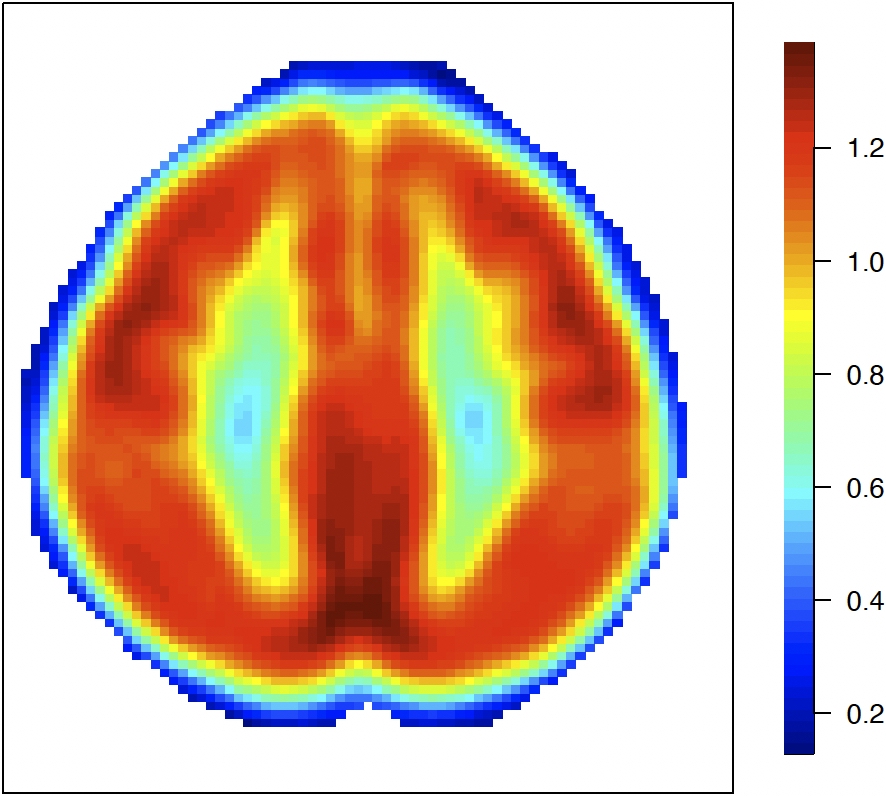

For the Hilbert-valued component, we first consider a 2D imaging setting. To mimic the full complexity of the real data and illustrate the performance of the proposed method in a challenging scenario with complicated patterns, we use the leading empirical basis functions obtained from the real data analysis in Section 6. To be specific, we construct the imaging data as Zi(s1,s2)=j=16λj1/2Uijϕj(s1,s2)Z_{i}(s_{1},s_{2})=\sum_{j=1}^{6}\lambda_{j}^{1/2}U_{ij}\phi_{j}(s_{1},s_{2}) on a 79×9579\times 95 pixel grid, where the eigenvalues (λ1,λ2,λ3,λ4,λ5,λ6)=(3.5,3,2.5,2,1.5,1)(\lambda_{1},\lambda_{2},\lambda_{3},\lambda_{4},\lambda_{5},\lambda_{6})=(3.5,3,2.5,2,1.5,1) and (Ui1,,Ui6)(U_{i1},\ldots,U_{i6})^{\top} follows MVN(06,I6)\text{MVN}(0_{6},I_{6}). The basis functions {ϕj}j=16\{\phi_{j}\}_{j=1}^{6} are the leading six principal component bases that are selected by PVE from the real data analysis; see Section 6.1 for more details. Figure 5.1 (top row) and Figure 6.1 (left three columns) display the plots of these basis functions. We set γ0=1.5ϕ1+ϕ2+2ϕ3+2.5ϕ4+1.5ϕ5+3ϕ6\gamma_{0}=1.5\phi_{1}+\phi_{2}+2\phi_{3}+2.5\phi_{4}+1.5\phi_{5}+3\phi_{6}.

Refer to caption Refer to caption Refer to caption Refer to caption Refer to caption Refer to caption

ϕ1\phi_{1}\penalty 10000\ \penalty 10000\ ϕ2\phi_{2} ϕ3\phi_{3} ϕ4\phi_{4}\penalty 10000\ \penalty 10000\ ϕ5\phi_{5} ϕ6\phi_{6}

ϕ^1\widehat{\phi}_{1}\penalty 10000\ \penalty 10000\ ϕ^2\widehat{\phi}_{2} ϕ^3\widehat{\phi}_{3} ϕ^4\widehat{\phi}_{4}\penalty 10000\ \penalty 10000\ ϕ^5\widehat{\phi}_{5} ϕ^6\widehat{\phi}_{6}

Figure 5.1: Comparison of true basis functions {ϕj}j=16\{\phi_{j}\}_{j=1}^{6} (top) and their estimates {ϕ^j}j=16\{\widehat{\phi}_{j}\}_{j=1}^{6} (bottom) for a randomly selected iteration with n=2000n=2000 in the 2D imaging setting.

The estimates of the basis functions are shown at the bottom of Figure 5.1, which is selected randomly from a single iteration. The figure shows that with n=2000n=2000 observations, the estimated basis functions (bottom row) closely reproduce both the pattern and magnitude of the true functions (top row), providing empirical validation of Theorem 4. In addition, Table 5.1 presents the estimation accuracy of the six eigenvalues (λ1\lambda_{1} through λ6\lambda_{6}) and the estimated number of eigenvalues under the PVE (m^n\widehat{m}_{n}) criterion. We observe that MSEs for all eigenvalues decrease as sample size increases across both correlation scenarios, demonstrating improved estimation precision with larger samples. The results in Table 5.1 further support the conclusions in Theorem 4 and Corollary 3.